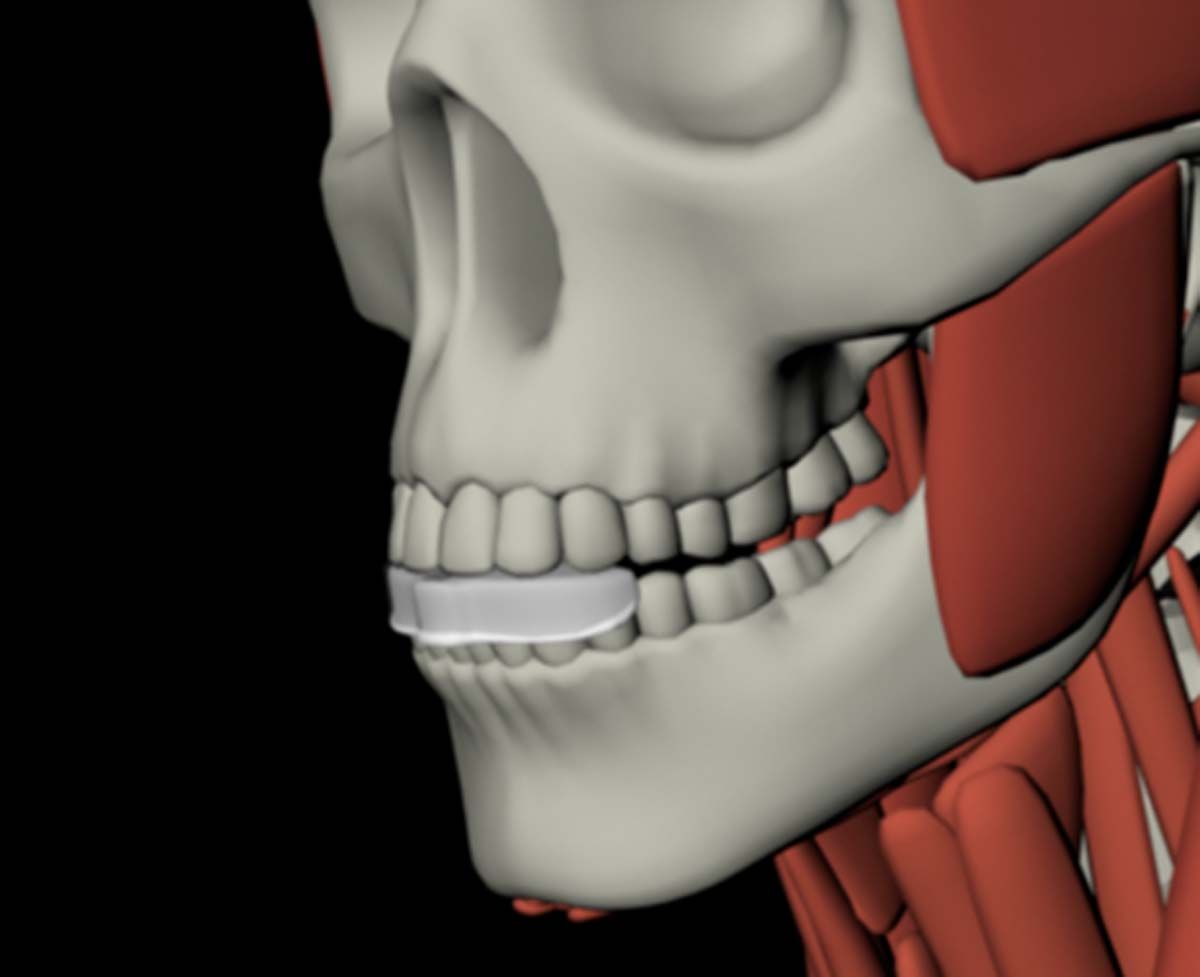

Suppose CBCT has revealed that the issue your patient is experiencing requires a specialist. A 3D scan tells me when it is best to refer treatment, but that can be frustrating and confusing to a patient who was not expecting a second appointment at another office. In that case, the 3D scan lets me prepare patients for the next steps. Yes, they are being sent to a specialist, but they will have realistic expectations about what the next doctor might find and recommend for treatment. Because I also send the scan to the specialist, there are no surprises for anybody; patients do not feel like they are arriving at another office only to be blindsided.

The CBCT revealed the extent and solidified the opportunity to make the correct clinical decision